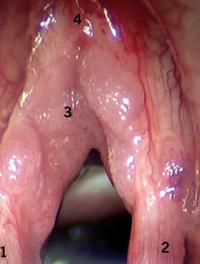

Les ichtyoses sont des anomalies héréditaires de kératinisation évoluant toute la vie. Les caractères cliniques, le mode de transmission et l’étude histologique permettent de classer la plupart des ichtyoses évoluant sans contexte clinique particulier et celles accompagnant d’autres troubles neuropsychiques, ophtalmologiques, etc., beaucoup plus rares.